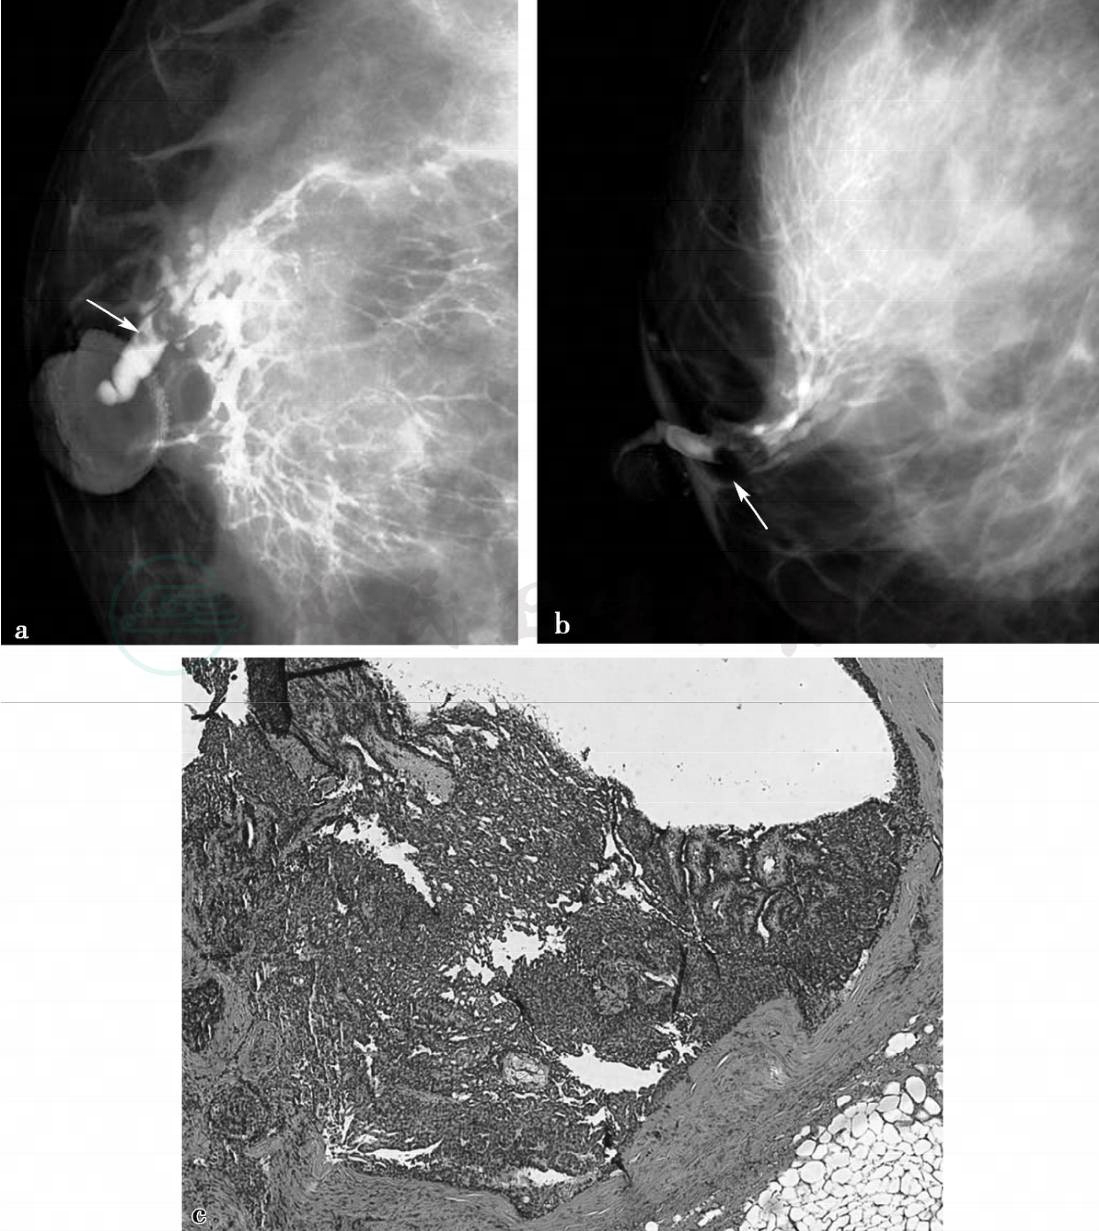

图1 图1a,右乳X线CC位(RCC)。图1b,右乳X线内外侧位(RML)。经右乳头血性溢液乳导管注入30%泛影葡胺注射液约0.4ml,注射阻力中等,行右乳CC、ML位摄片,右乳外侧乳导管及外上象限分支导管显影,导管发育呈枝干型,主导管距离乳头约为8mm处可见类椭圆形充盈缺损,边缘光滑,近端呈“杯口状”锐利(如图a、b箭头所示),分支导管轻度扩张,未见明显导管破坏征象。图1c,病理示镜下可见导管上皮增生呈乳头状(见文后彩图)